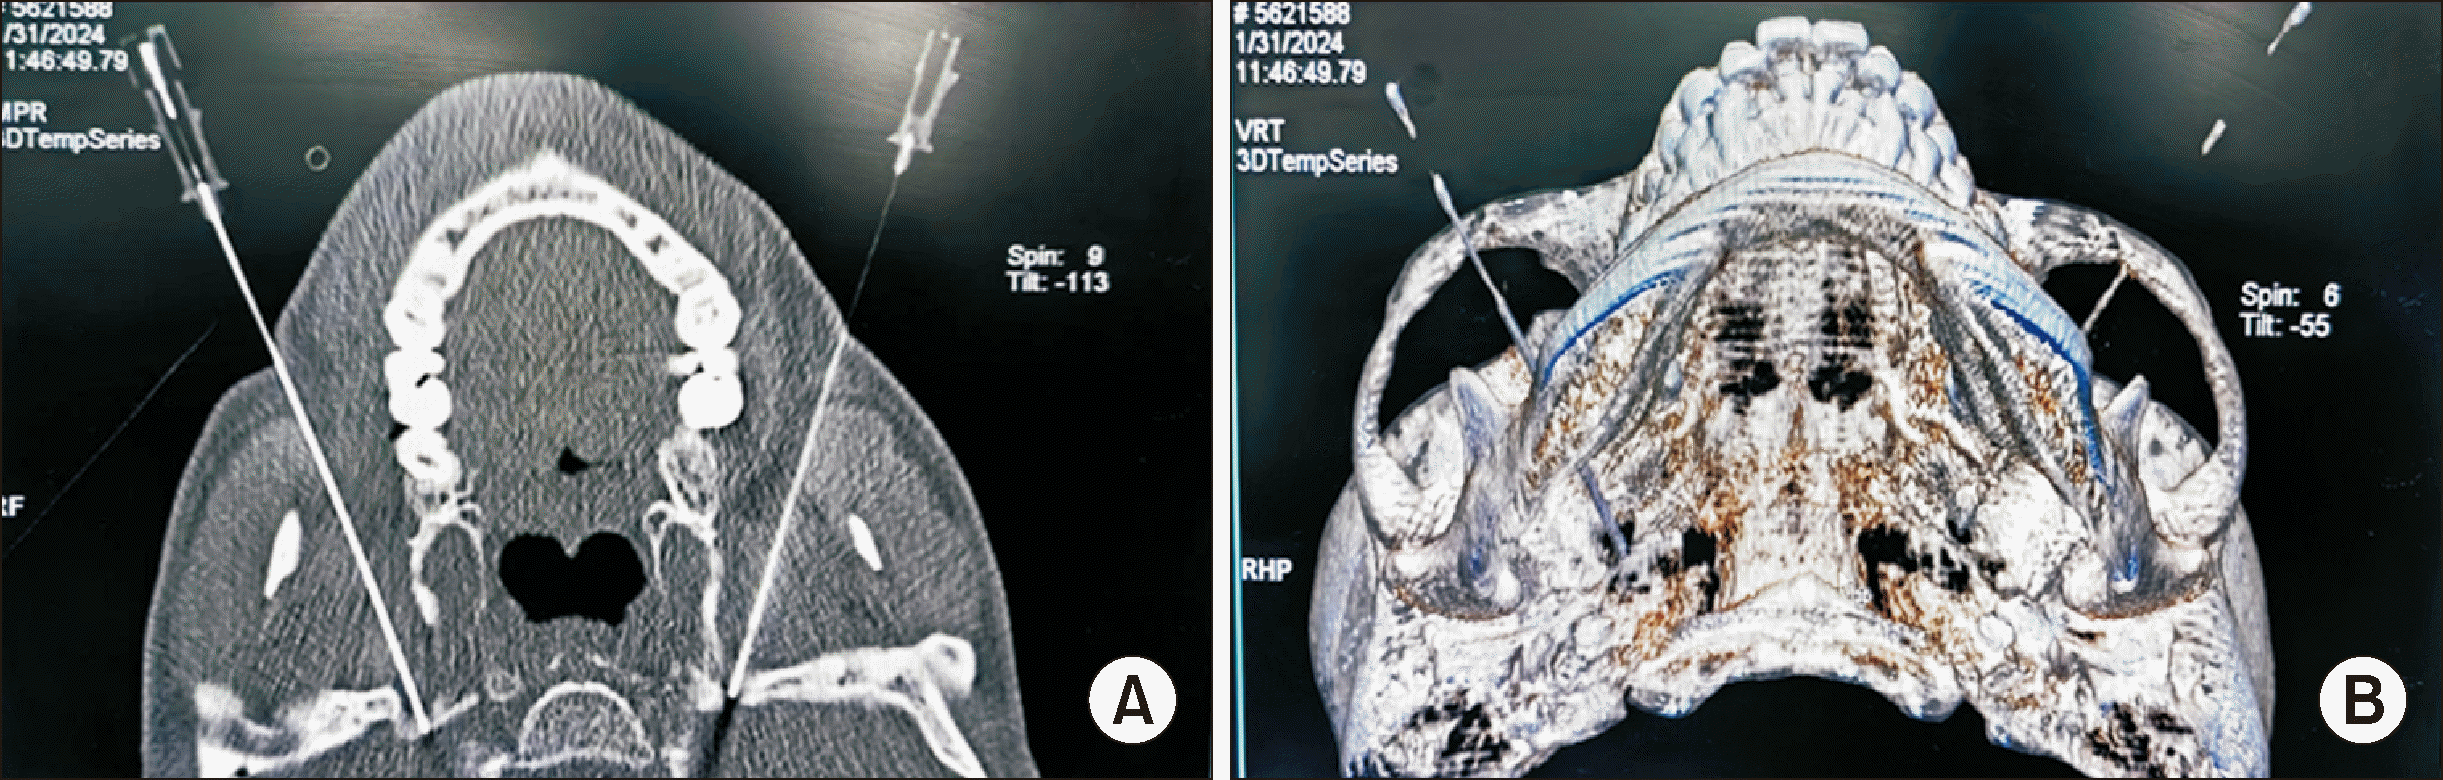

This study was approved by the ethics committee of the affiliated hospital (approval number: LS2019-013), and the patient provided written informed consent. Briefly, the patient was placed supine on the CT table, and a coronal CT scan was performed. The puncture path was designed after locating the bilateral foramen ovale (FO). Next, two radiofrequency needles were punctured into the bilateral FO according to the designed path (Fig. 1) [2,3]. Following this, a motor nerve stimulation test was performed at a low frequency (2 Hz), and stimulation at 0.5–1 mA induced tremors in the bilateral mandibles matching the electrical stimulation frequency. The patient was sedated via intravenous injection of propofol 1 mg/kg and fentanyl 1 µg/kg, followed by 60 seconds of continuous radiofrequency ablation at 70°C. Postoperative involuntary chewing was resolved, but this was accompanied by mild numbness and sensory reduction in skin areas innervated by the trigeminal nerve.

Fig. 1

Radiofrequency ablation of mandibular branch of trigeminal nerve by bilateral foramen ovale puncture under CT guidance to treat masticatory muscle spasm. (A) The successful image of bilateral foramen ovale puncture. (B) CT three-dimensional reconstruction image after successful puncture of the bilateral foramen ovale, with bilateral RF needle points located in the foramen ovale.